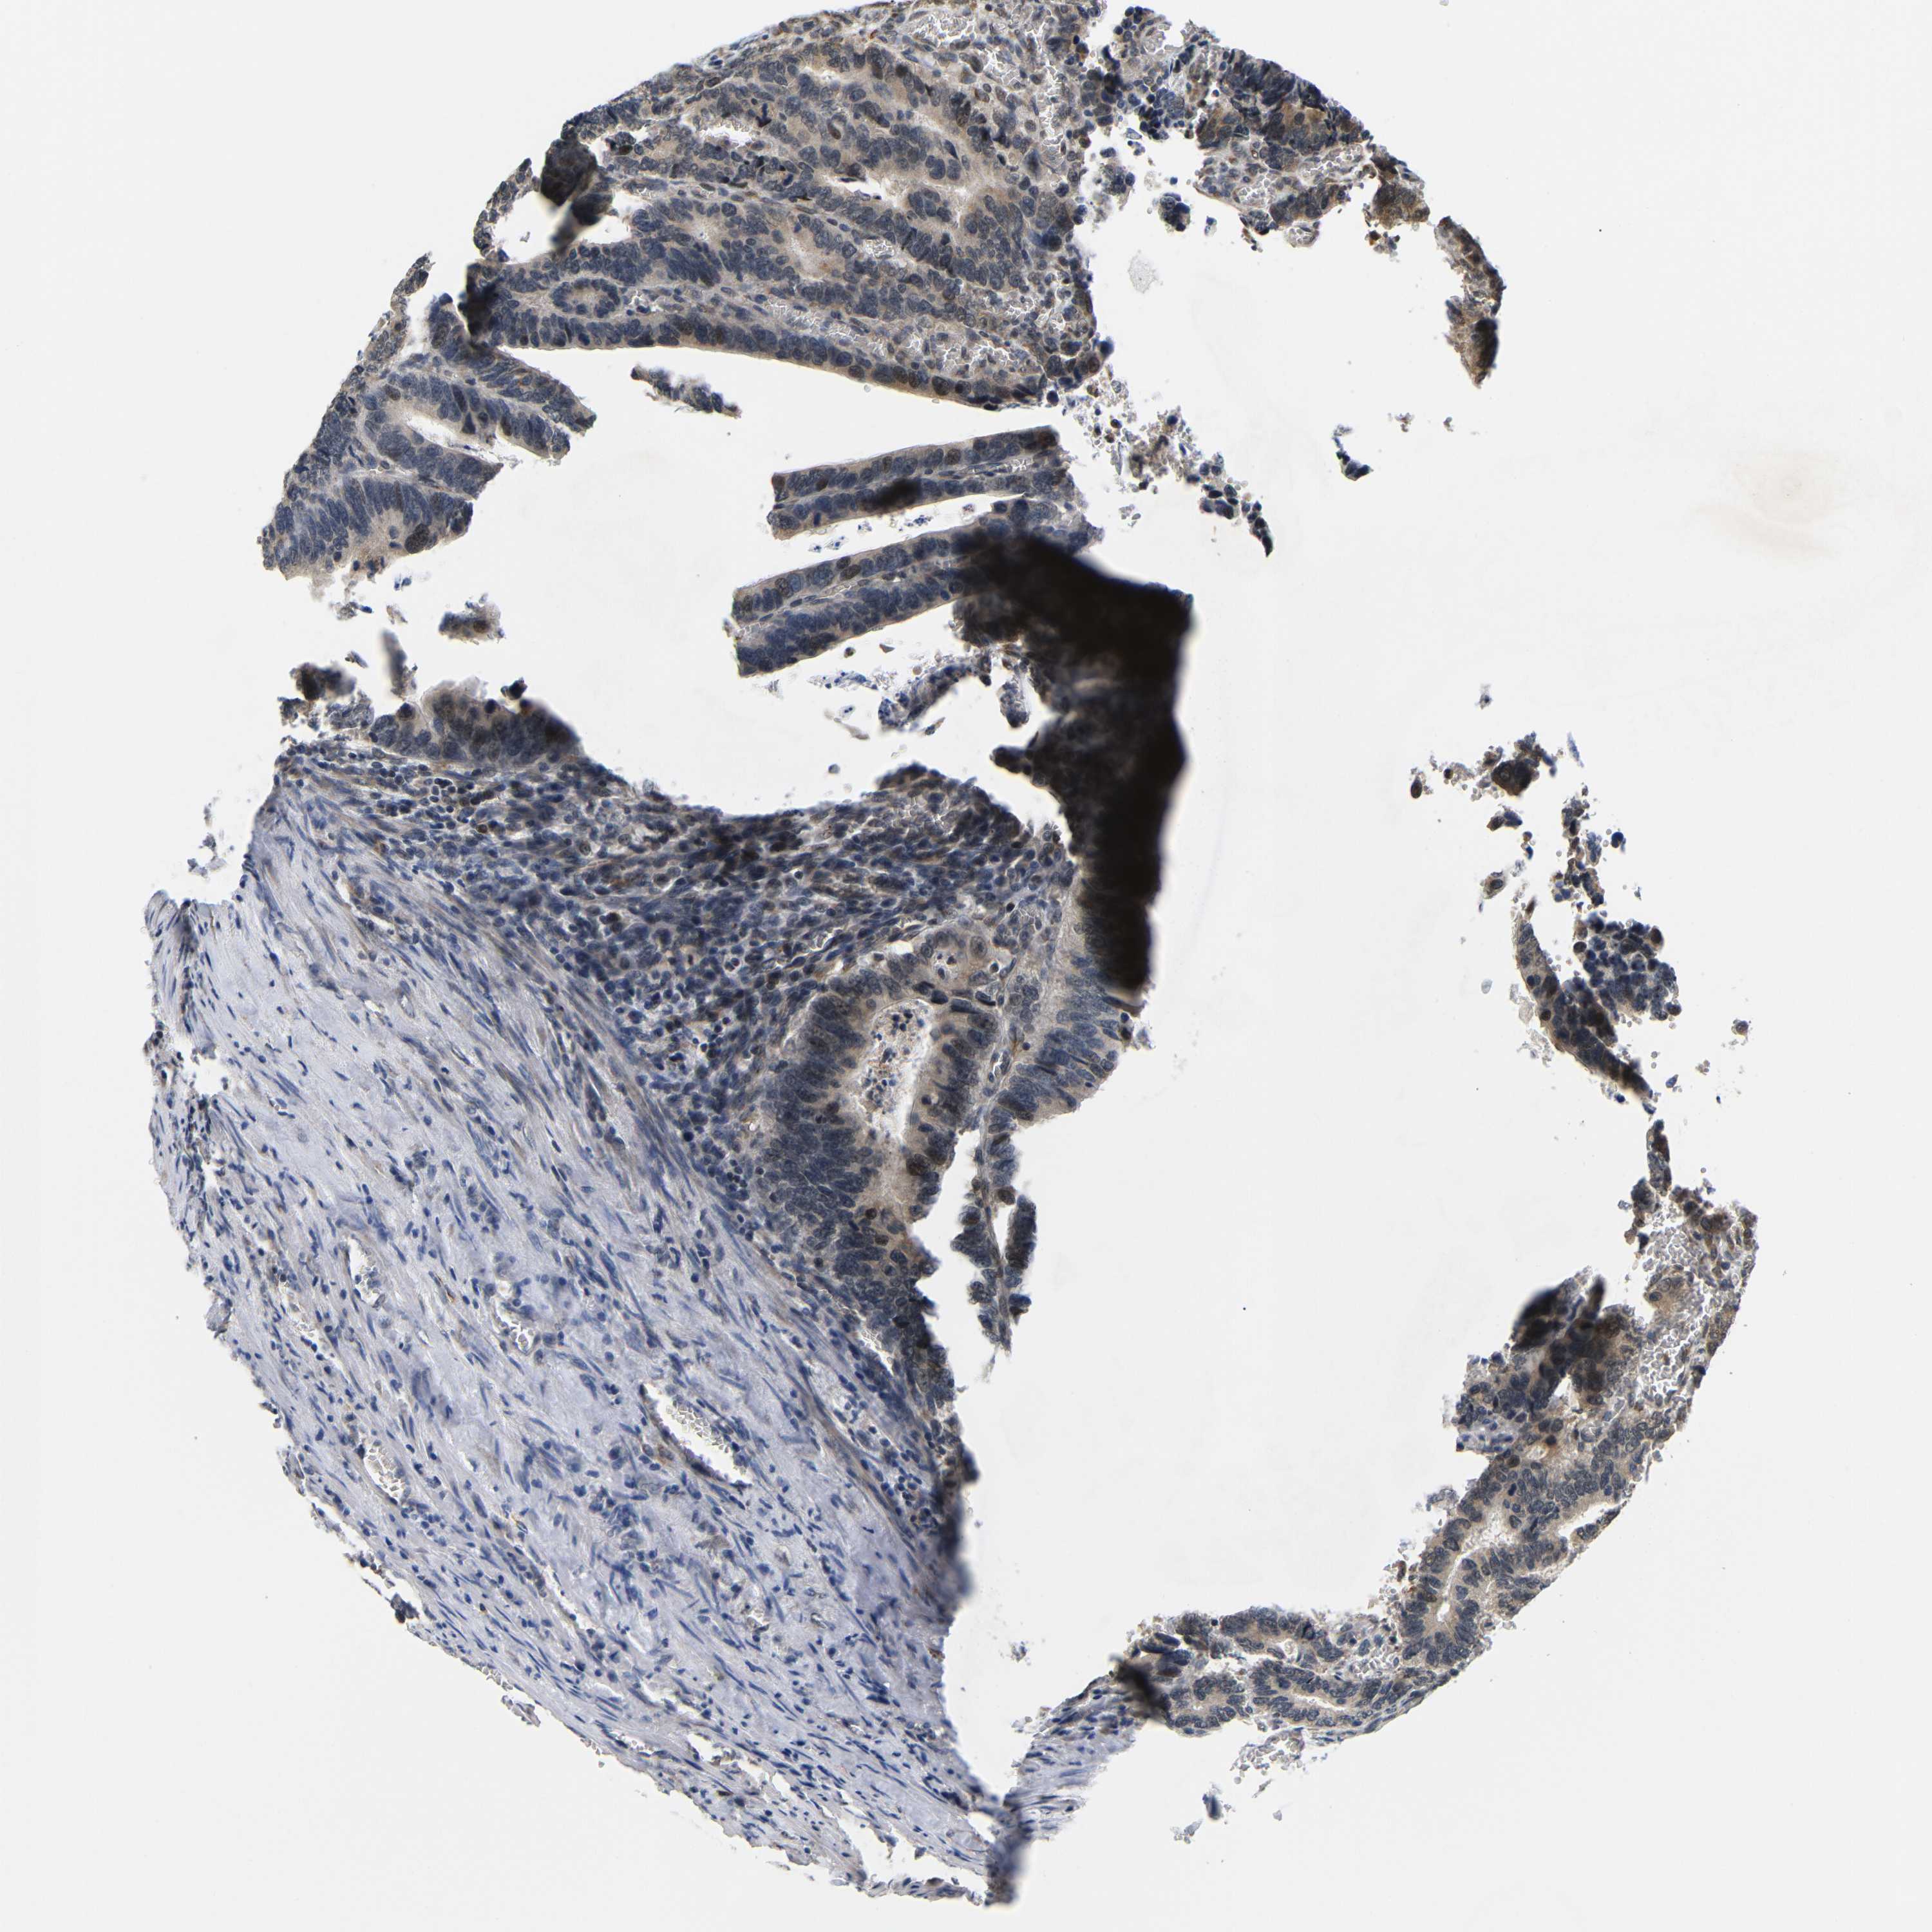

CANCER COLORECTAL CANCER Show tissue menu

Colorectal cancer

Human cancer

Colon adenocarcinoma